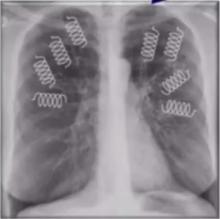

Emphysema: Endobronchial Volume Reduction [1]

Felix Herth of Thoraxklinik at the University of Heidelberg, Germany, discusses the current approaches available for managing emphysema.